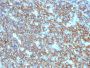

Applications IHC

IHC, FFPE (verified)

Recognizes a protein of 30-33 kDa, which is identified as CD20. It is a non-Ig differentiation antigen of B-cells and its expression is restricted to normal and neoplastic B-cells, being absent from all other leukocytes and tissues. CD20 is expressed by pre B-cells and persists during all stages of B-cell maturation but is lost upon terminal differentiation into plasma cells. This antibody can be used for immunophenotyping of leukemia and malignant cells, B lymphocyte detection in peripheral blood and B cell localization in tissues. It reacts with the majority of B-cells present in peripheral blood and lymphoid tissues and their derived lymphomas. In lymphoid tissue, germinal center blasts and B-immunoblasts are particularly reactive. It is a reliable antibody for ascribing a B-cell phenotype in known lymphoid tissues. Rarely, CD20-positive T-cell lymphomas have been reported. Reactivity has also been noted with Reed-Sternberg cells in cases of Hodgkin's disease, particularly of lymphocyte predominant type. Primary antibodies are available purified, or with a selection of fluorescent CF® Dyes and other labels. CF® Dyes offer exceptional brightness and photostability. Note: Conjugates of blue fluorescent dyes like CF®405S and CF®405M are not recommended for detecting low abundance targets, because blue dyes have lower fluorescence and can give higher non-specific background than other dye colors.

Positive Control

Daudi, Raji, and U266, and human lymphocytes. Lymph nodes and tonsils.

B-cells|Lymphocytes

Leukemia/lymphoma

IHC (FFPE) (verified)